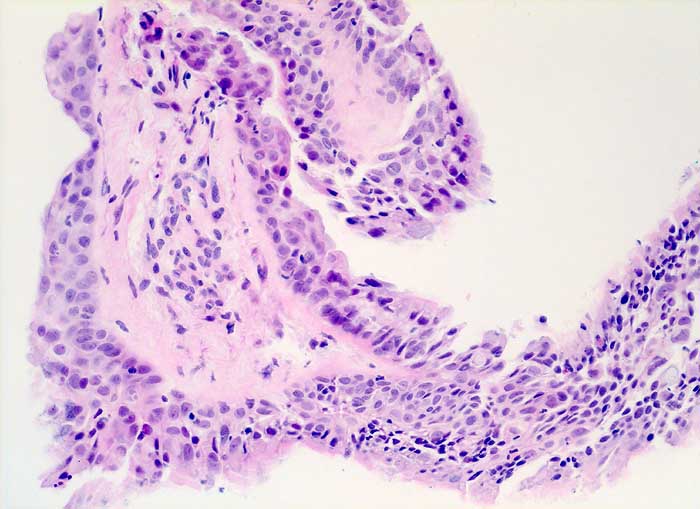

strahleninduzierte Kernatypien

Ausgeprägte Kernpolymorphie und Kernvergrösserung des respiratorischen Epithels bei erhaltener Kern-Zytoplasmarelation.

NSCLC neoadjuvante Therapie

200